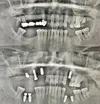

Implant tedavisi